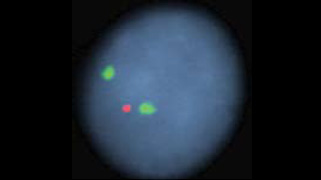

1313q14.3LSI D13S319 SpectrumOrange            1VIEW IMAGE

1313q34LSI 13q34 SpectrumGreen            2VIEW IMAGE